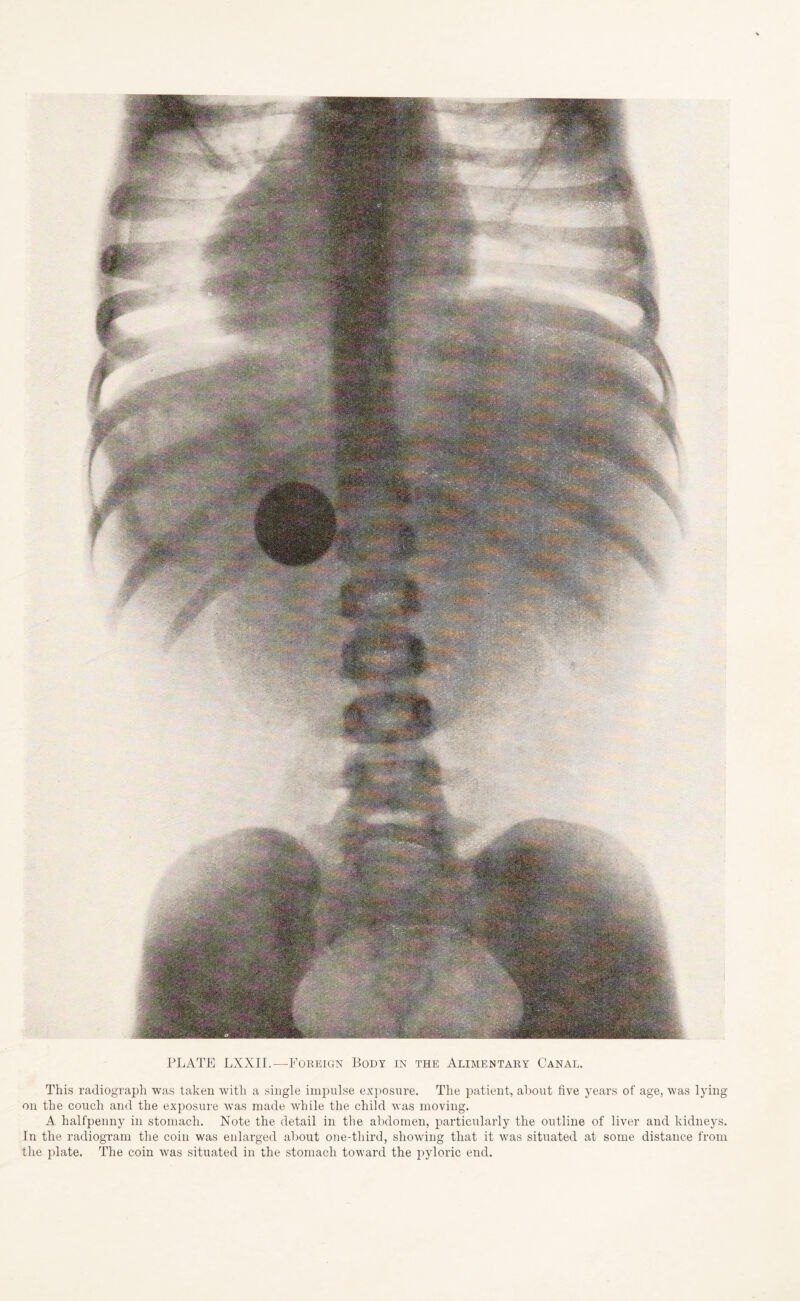

485/544 page 367